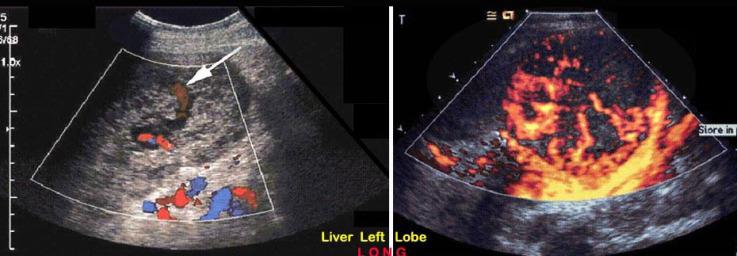

Patient with cirrhosis

Hepatocellular Carcinoma

solid

multiple

diffuse